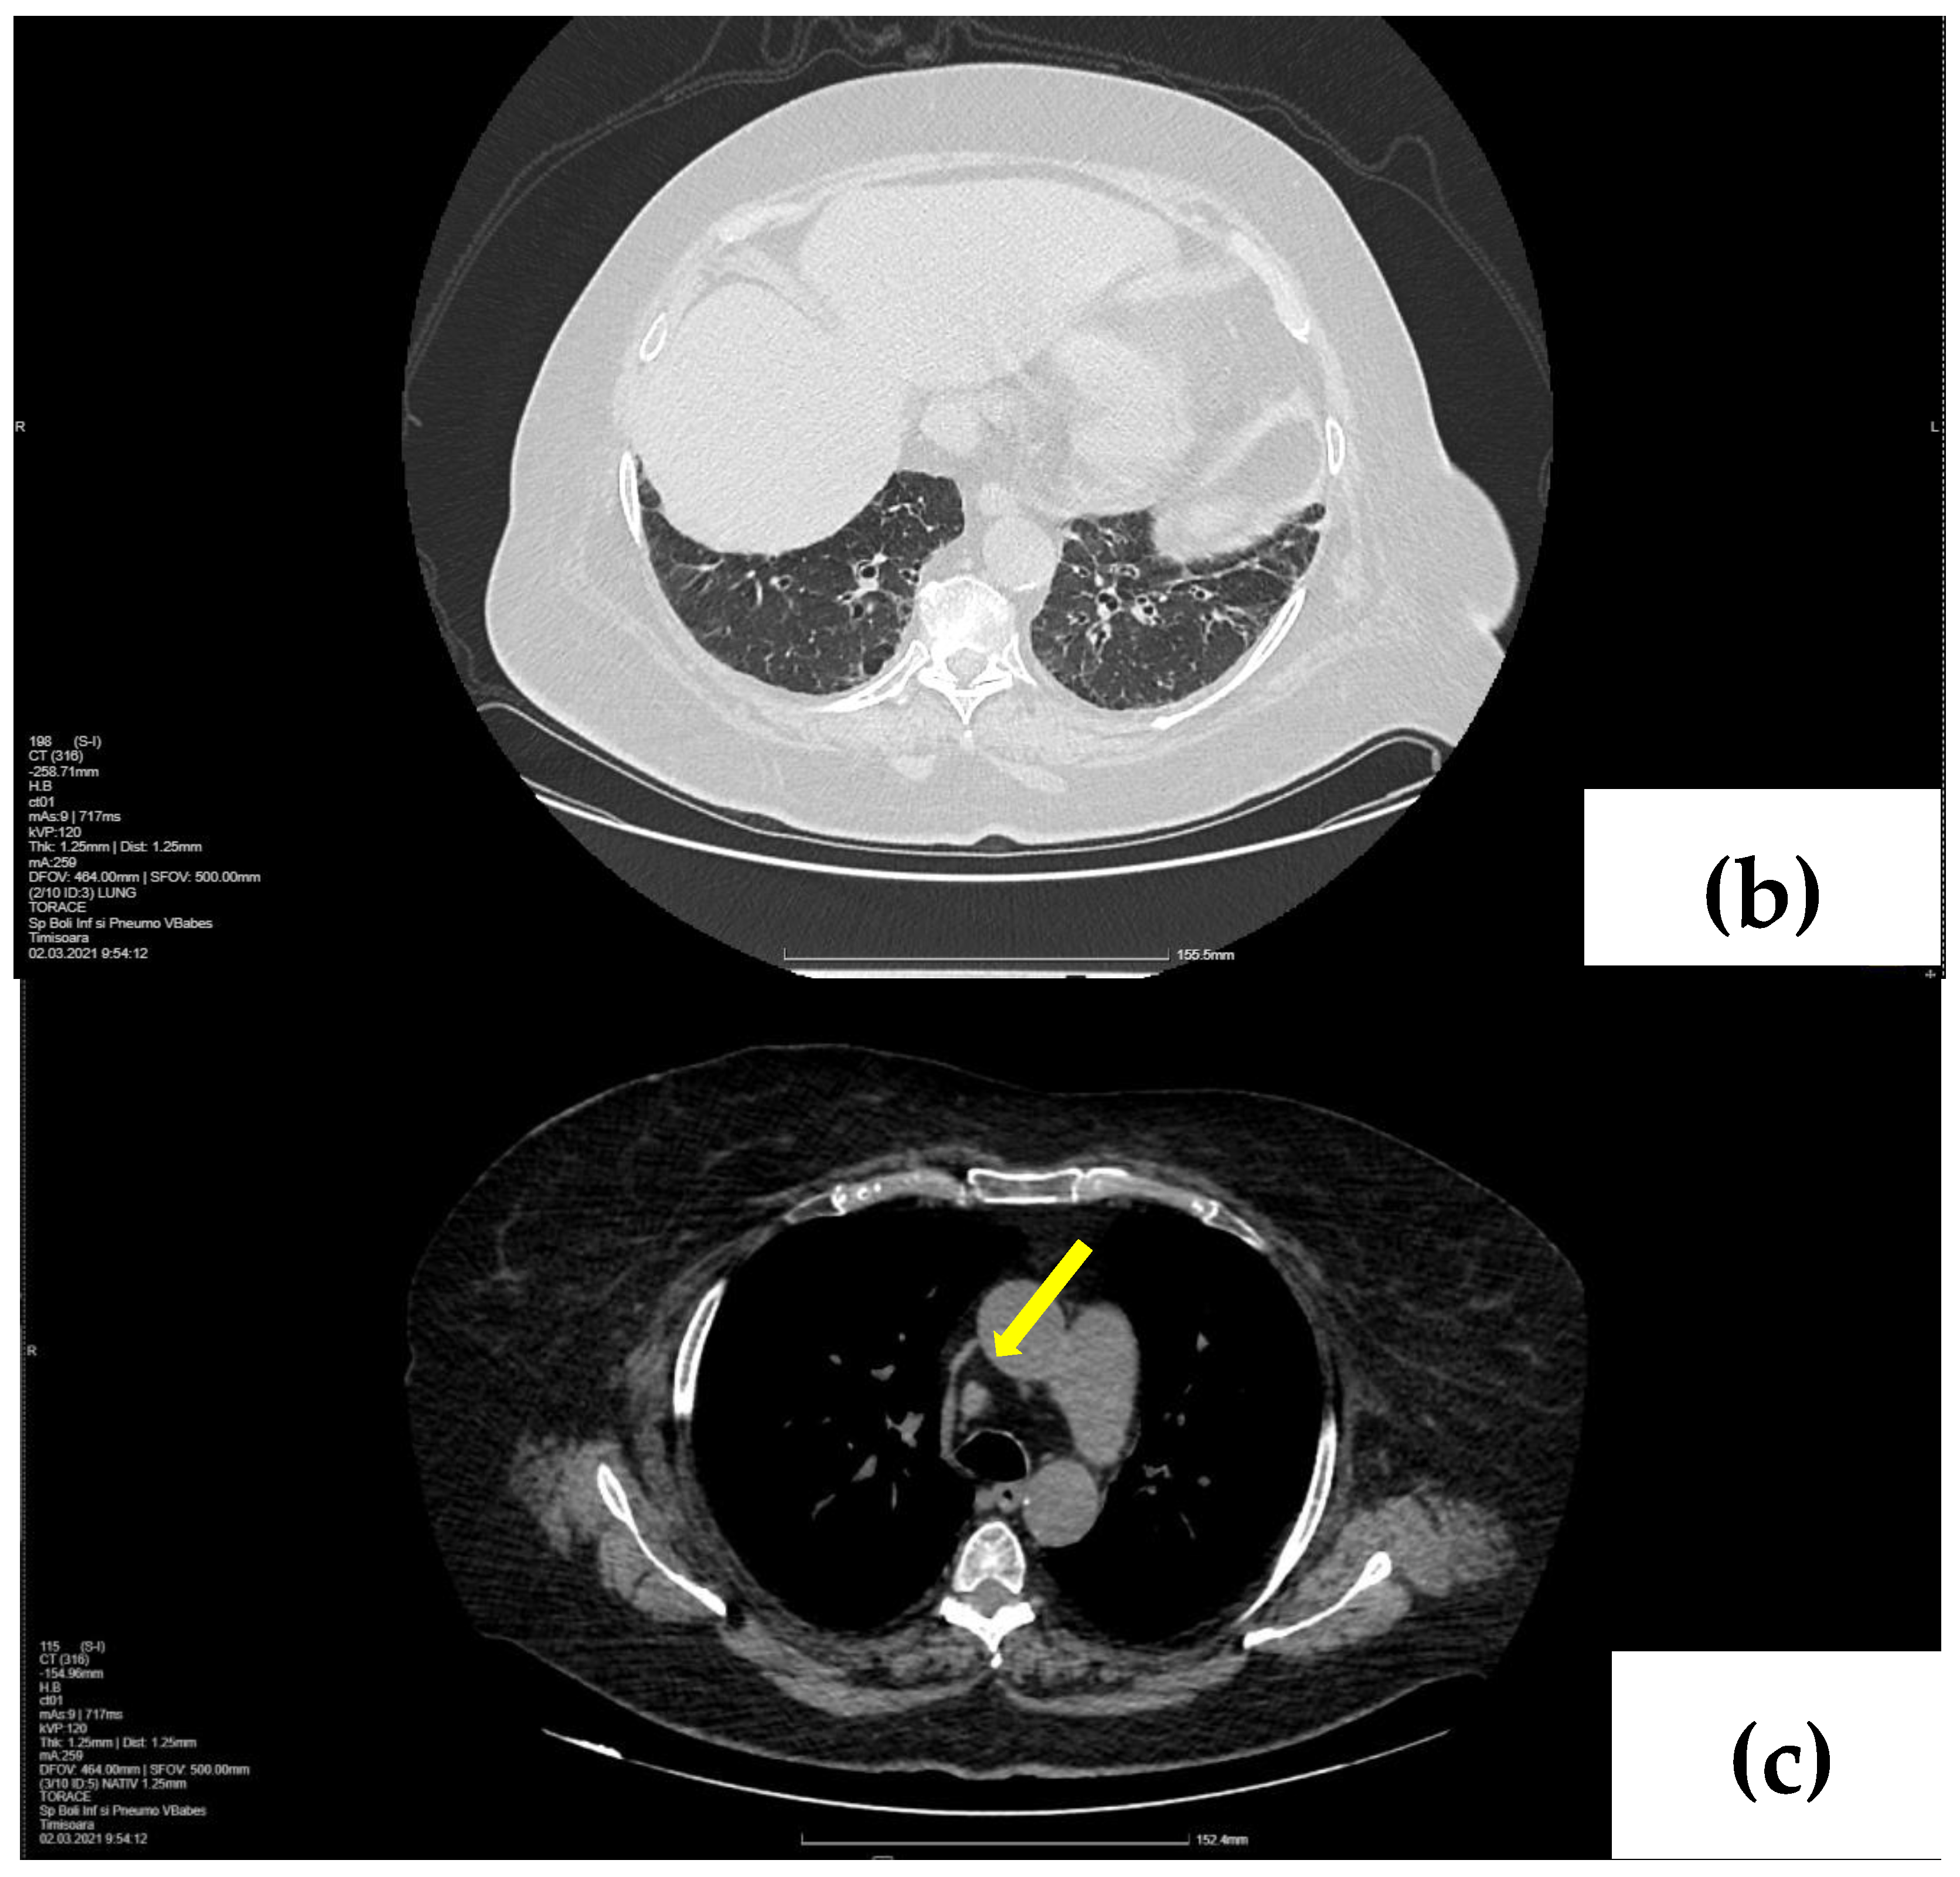

2.2. Treatment and Outcome

2.1. Laboratory, Radiological, and Histological Examinations